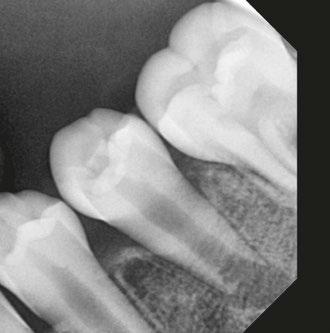

A 10-year-old female patient with a history of swelling and pain associated with tooth No. 20 was referred to our office. The patient exhibited severe dental anxiety. Upon clinical evaluation, a dens evaginatus was noted on the occlusal surface of the tooth (Figure 1). The tooth was sensitive to percussion, palpation, and bite stick while cold testing yielded no response. A periapical radiograph and CBCT scan (Carestream 9600) revealed a wide open apex and evidence of apical periodontitis, leading to the

Figure 1 (left): Dens evaginatus noted on the occlusal surface. Figure 2 (right): Preoperative periapical radiograph of tooth No. 20 showing evidence of apical periodontitis and a wide open apex

diagnosis of a necrotic pulp and symptomatic apical periodontitis of tooth No. 20 (Figures 2 and 3).

Figure 3 (left): Preoperative CBCT scan of tooth No. 20 showing evidence of a wide open apex. Figure 4 (right): Bleeding noted in the canal immediately after removing the GentleWave platform

In this case report, we present a 10-year-old patient with a wide open apex and a dens evaginatus.5 This case was successfully managed with single visit regenerative endodontics using the GentleWave® System (Sonendo®).6 The outcomes demonstrate not only the feasibility but also the efficacy of this approach in achieving favorable clinical and radiographic results in pediatric patients.